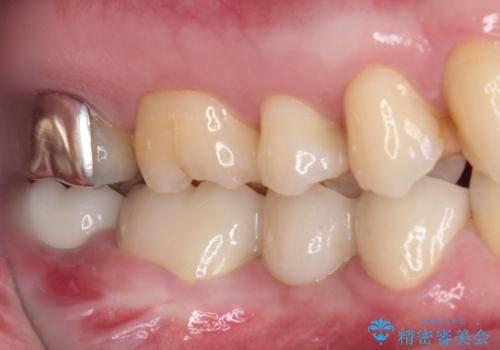

- 近医で奥歯が割れているので抜歯が必要と言われたとのことで来院された患者様です。

診断の結果、歯根が縦に破折しており抜歯が必要な状態でした。

抜歯してからインプラント埋入までには時間がかかるため、その間に下顎左右臼歯の金属のブリッジをオールセラミックへ変えていくこととしました。